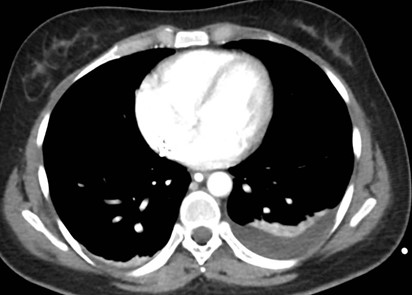

Caso 2

Paciente femenina de 48 años de edad que ingresa a Hospital Sanatorio Franchin por síntomas de cefalea y mareos, cuadro que se hace progresivo, presentando síncopes y posteriormente alteración del estado de conciencia. Los exámenes clínicos revelan una glucosa de 40 mg/dl, concomitante con insulina alta y péptido C elevado. Ingresa de forma programada para realización de duodeno pancreatectomía el 29 de mayo de 2021. Imágenes diagnósticas muestran estudio trifásico de tomografía de abdomen, lesión nodular en la cabeza del páncreas con ávido realce en fase arterial que en resonancia magnética se observa hiperintensa en T2, presenta restricción con la difusión y caída de la señal en el ADC. Además presenta realce tras la administración de contraste con gadolinio.

Estudio histopatológico reveló tumor neuroendocrino bien diferenciado grado 1.